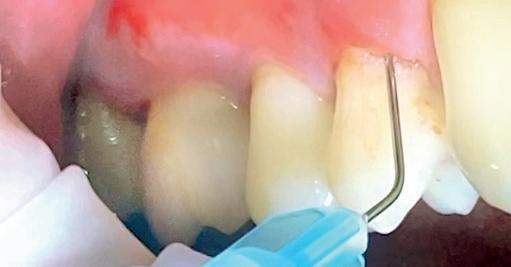

Een 48-jarige gezonde vrouw presenteerde zich in de nazorgfase 2 jaar na initiële behandeling met pockets van 6–7 mm en furcatieproblematiek bij de 47 en 46 (afbeelding 1.1 en 1.3). Bloeding bij sonderen was aanwezig, maar de patiente wilde geen chirurgische behandeling. Ze hield er een keurige mondhygiëne op na en kwam trouw iedere drie maanden voor nazorg.

De pockets werden onder lokale anaesthesie behandeld met een combinatie van ultrasoon en handinstrumentarium volgens de hierboven beschreven methode. De natriumhypochloriet/aminozuur-gel werd vijfmaal aangebracht en na iedere applicatie mechanisch verwijderd. Daarna werd de pocket gevuld met cross-linked hyaluronzuur.

Na 6 maanden was de pocketdiepte teruggebracht tot 3 mm en was er geen bloeding na sonderen waarneembaar. Een recessie van 2 mm was aanwezig. Röntgenologisch was er nieuw bot zichtbaar (afbeelding 1.2 en 1.4).